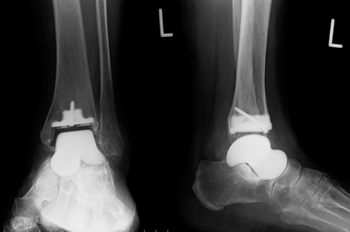

変形性関節症や骨壊死などによって傷んだ関節の表面を、人工の関節に置き換える手術です。

この手術により、長年続いていた関節の痛みが大幅に軽減され、生活の質(QOL)の改善が期待できます。